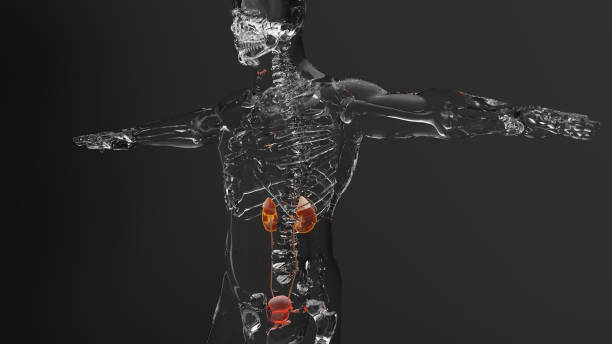

요로결석은 요로계통에서 생긴 결석물로, 많은 이들이 경험하는 통증과 불편을 초래할 수 있습니다. 이를 예방하기 위해서는 음식 선택이 매우 중요합니다.

특정 음식은 요로결석 생성에 영향을 줄 수 있으며, 이러한 음식을 피하는 것이 중요합니다.